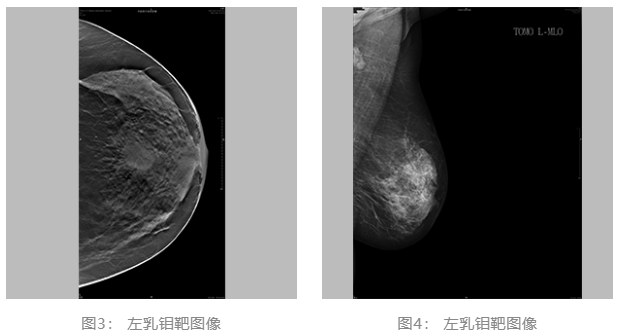

2021.06.30乳腺体层成像:双乳ACR c型。左乳肿块,BI-RADS 4C 类。双乳腺体增生样改变,BI-RADS 2类。(图3、4)